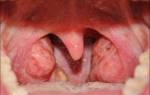

Хронический тонзиллит не дает покоя многим людям из-за постоянного обострения болезни. Он по-разному выражается у пациентов, но хорошего ничего не приносит, кроме боли в горле, ослабления иммунитета и долговременного лечения. Существует несколько методов лечения этой болезни, но мы рассмотрим подробнее такую процедуру, как промывание миндалин.

Промывание лакун миндалин. Промывание лакун — медицинская процедура, при которой удаляют гнойные пробки из лакун (углублений) небных миндалин.